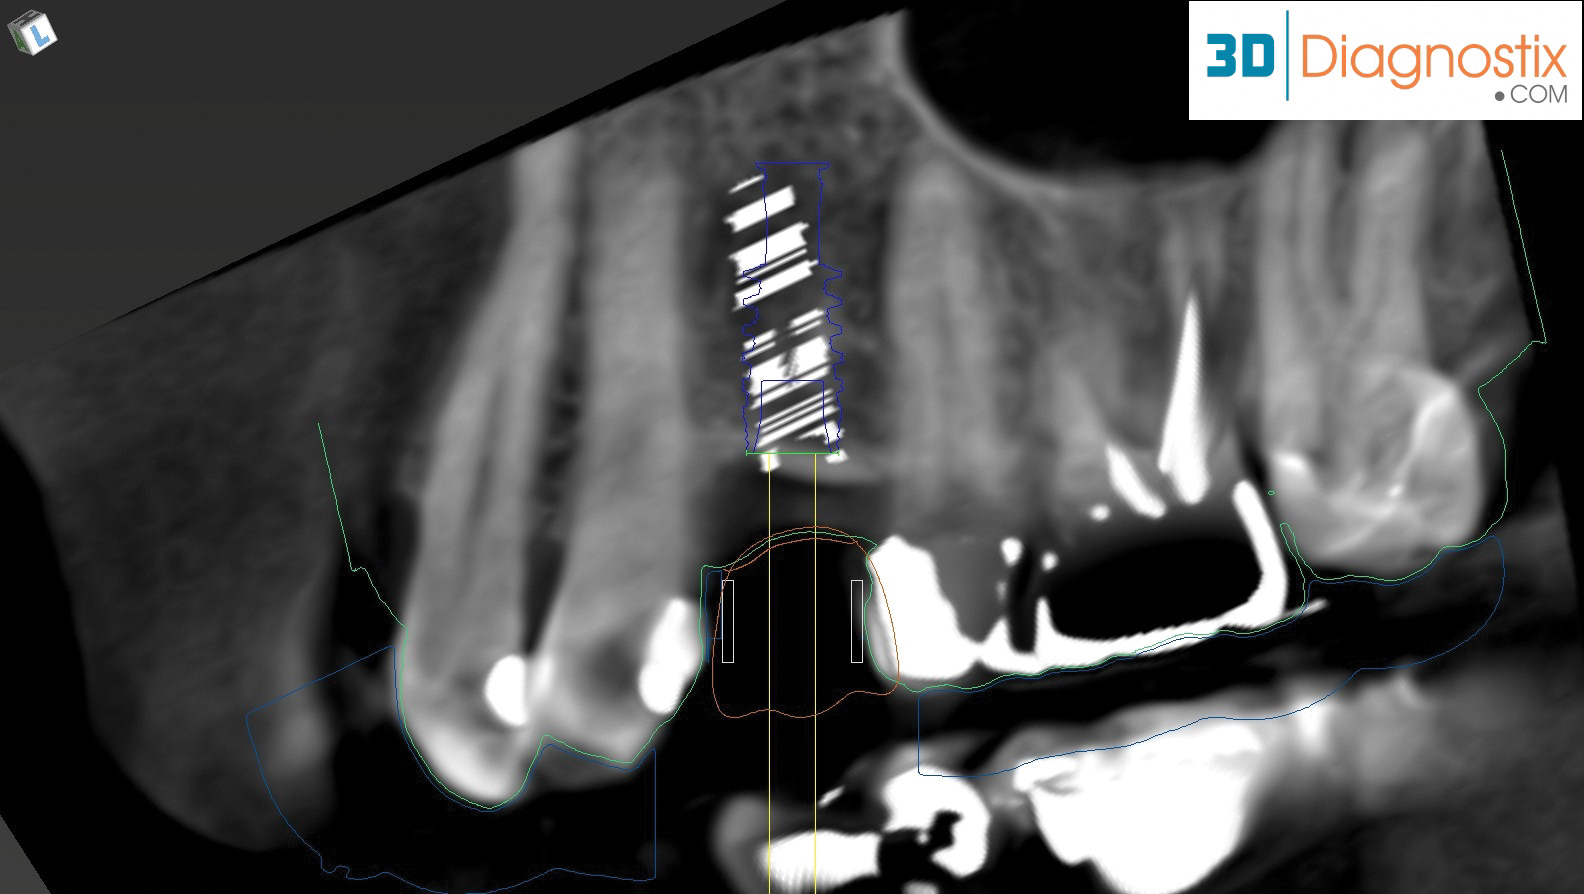

With a digital patient record system and IOS, software can be used to incorporate CBCT images and data to facilitate implant and other dental surgical treatment planning. If a restorative dentist has both an IOS system and a CBCT, the two data files could be merged and forwarded to the dental laboratory and oral surgeon/periodontist for treatment planning (Figure 7) to determine ideal implant placement based on proposed restorative needs and for fabrication of an implant surgical guide.14

In this type of workflow model, a CBCT scan is made showing the area of concern, along with an IOS or a benchtop scan of a model or impression. This enables thorough evaluation of the patient’s condition, as well as planning of ideal restorations from esthetic and functional perspectives. The intraoral information can be merged with the CBCT scan to further evaluate whether the proposed treatment is appropriate or whether additional procedures (eg, bone grafting) should be considered (Figure 8 through Figure 10). These images can then be used for collaboration with the laboratory and referral specialists, either via cloud-based file sharing or electronic transmission, to ensure that a restoratively driven approach is undertaken for ideal implant placement.14,19

Fig 9. By merging CBCT files with IOS files and using implant planning software, dental professionals can plan all components of the implant/restoration procedure in advance for a restoratively driven approach: CBCT, IOS, and CAD merged and overlayed as one (Fig 9); implant placement and implant guide CAD (Fig 10).

Figure 9

Fig 10. By merging CBCT files with IOS files and using implant planning software, dental professionals can plan all components of the implant/restoration procedure in advance for a restoratively driven approach: CBCT, IOS, and CAD merged and overlayed as one (Fig 9); implant placement and implant guide CAD (Fig 10).

Figure 10